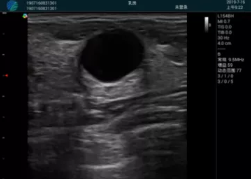

甲狀腺囊性結(jié)節(jié),囊壁鈣化,透聲好

甲狀腺囊性占位